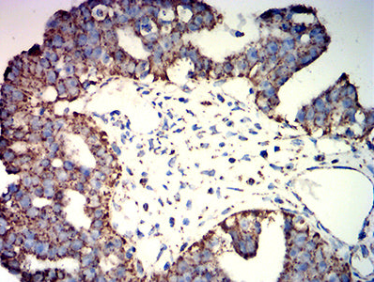

ATP5F1A Mouse Monoclonal antibody[3A6B9]

IHC    1/200 - 1/1000